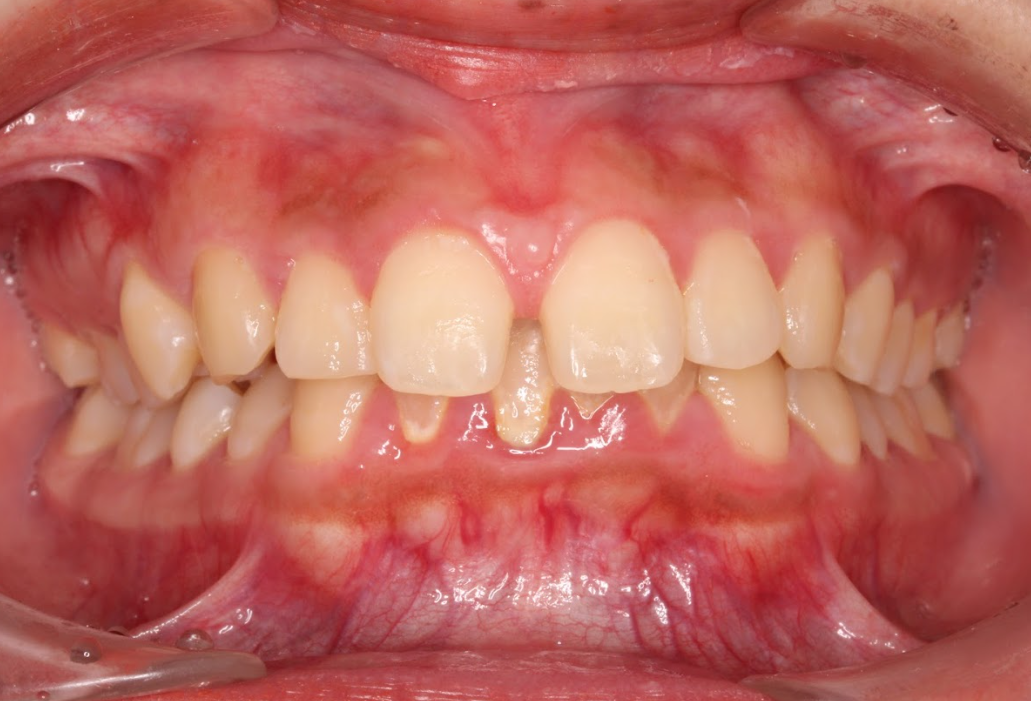

軽度のガタつき

上の前歯が軽く重なり合っていたり、並びが不揃いになっている「軽度のガタつき」も、インビザラインで上だけの矯正が可能です。このようなケースでは、歯を少しずつ正しい位置に移動させることで、整ったアーチ状の歯並びを改善できます。

歯の動きが小範囲で済むため、治療期間も比較的短く、費用も全体矯正より抑えられるメリットがあります。ただし、スペースが極端に不足している場合や、奥歯の位置に大きなズレがある場合は、部分矯正では限界があるため、全体矯正が適応されることがあります。